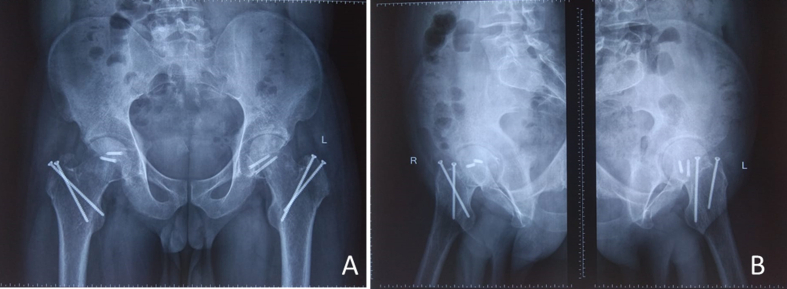

Fig. 6.

Follow-up radiograph at 24-month shows completely healed fracture without any evidence of osteonecrosis.